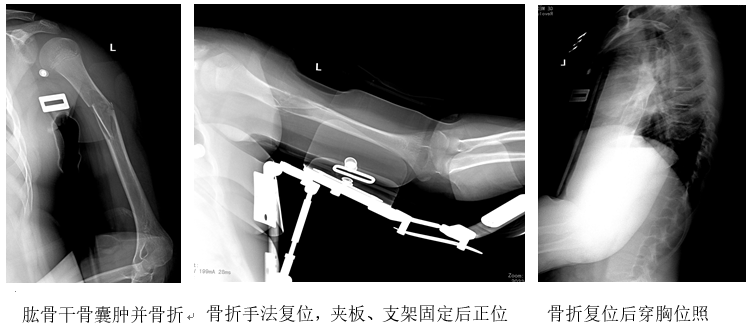

左上臂外伤后疼痛、肿胀、畸形、活动受限,经照片诊断为左肱骨干中段骨囊肿并发粉碎性骨折。多家医院都建议开放手术植骨内固定治疗,患儿及家长坚决拒绝手术,于伤后2天来诊。

检查:见患儿左上臂已用石膏托外固定,肱骨中段肿胀压痛,有纵轴叩击痛,外凸明显,前臂皮感正常、活动明显受限,手指活动及桡动脉搏动正常。

治疗组为患者制定了详细的非手术治疗方案。复位在手术室进行,在臂丛麻醉下施行手法复位:稍加对抗牵引、骨折断端端提挤按整复,C形臂X线透视见骨折达到解剖对位,随之实施了四合一夹板外固定(三点放置压垫),颈腕吊带悬挂前臂。

2天后照片复查,见骨折处稍向外成角,立即用手法挤按调整(未麻醉),加用定制的肩关节外展支架支撑上肢于水平位,照片复查显示骨折成角纠正。整复、固定完成后即开始口服中药,先期桃红四物汤加味以活血行气、消肿止痛,2周后直至伤后2个月,改用接骨续损之续骨活血汤口服。教会家长监督患儿握拳及手腕、手指的活动锻炼。住院2周时照片复查再未发生移位,遂出院。

复位2个月后照片显示骨折愈合,骨囊肿消失,遂去除外固定装置,恢复了正常学习和生活。当患儿及家长得知骨折完全愈合、骨囊肿也随之消失的消息时,都大喜过望。随诊1年,骨折愈合良好,骨囊肿无复发。

原发病灶导致的骨折端粉碎,使得骨折复位及固定难度增加,虽然骨折整复后对位对线良好,但极不稳定,次日就出现了骨折移位,只能再行手法调整,加用上肢外展支架(系定制支架)支撑后,上臂肌肉放松,骨折趋于稳定。此后每3~5天照片1次,又有2次发现轻微成角,都在增加压垫厚度后成角纠正,2个月后骨折处有大量骨痂形成。幸运的是,之后的照片显示骨囊肿也消失了,治疗取得了十分满意的效果。